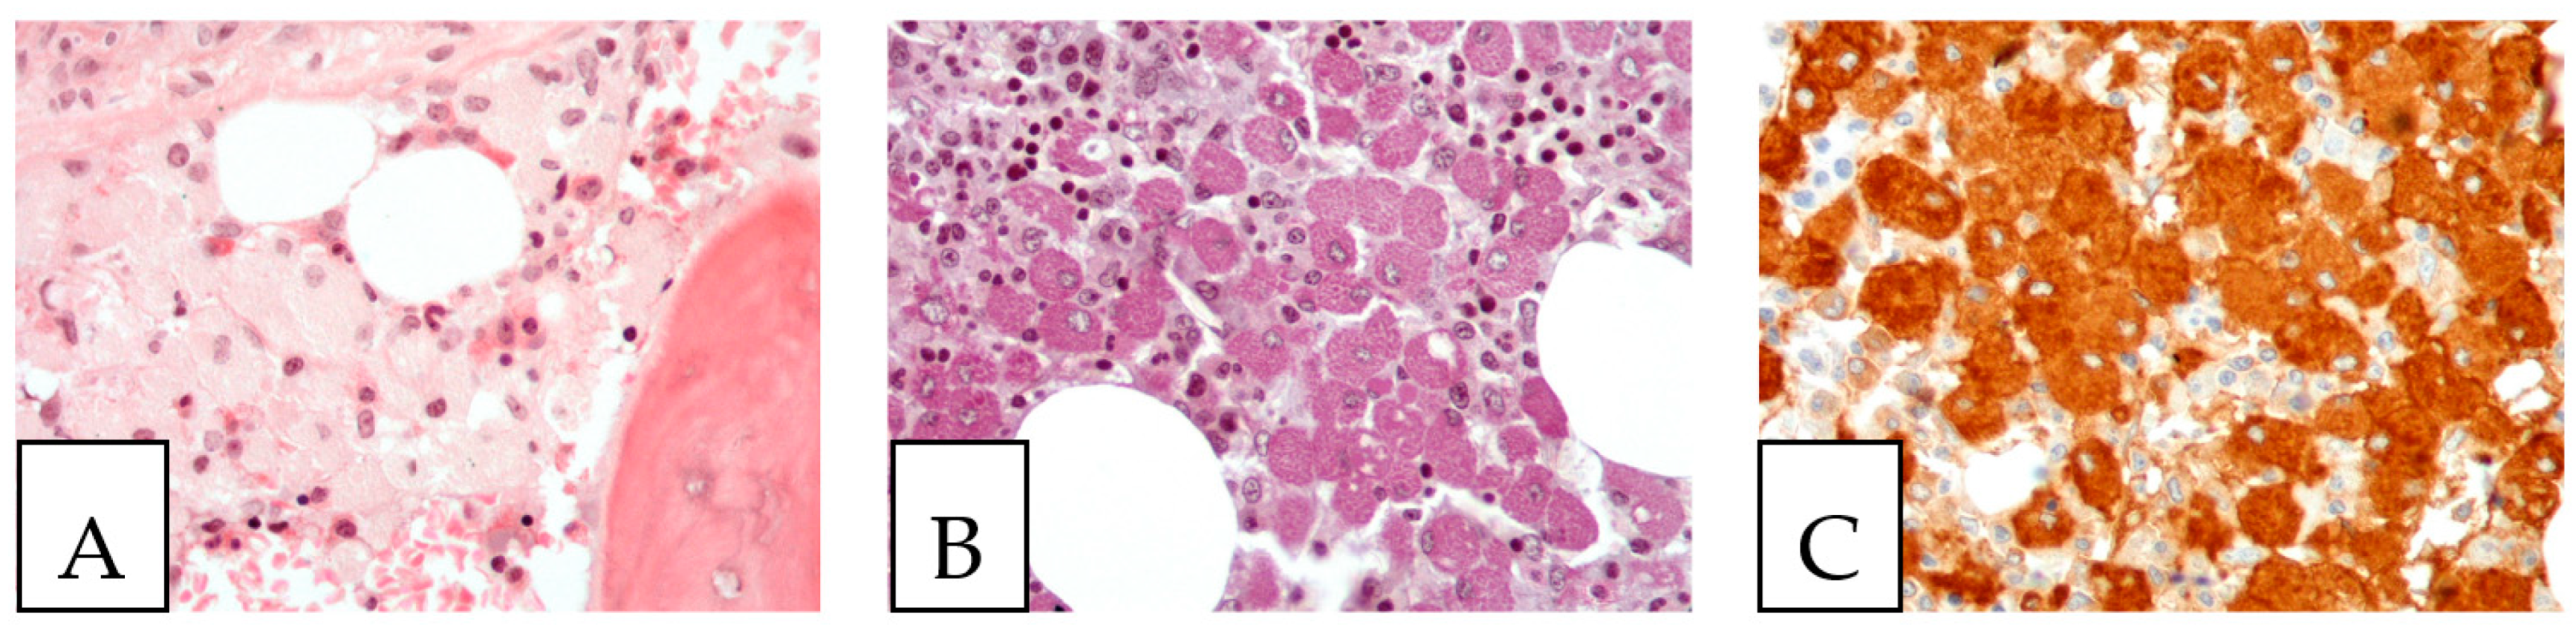

Gaucher disease, an autosomal recessive lysosomal storage disease, is characterized by the macrophagic accumulation of glucocerebroside affecting many organs, especially the liver, spleen, and bone marrow. It is due to an enzymatic defect, producing histologically the so-called crinkled-paper eosinophilic cytoplasm (Figure 7). In addition, some diseases, such as chronic myelogenous leukemia, can show bone marrow cells with similar morphological findings, called pseudo-Gaucher cells; based on that, some authors described crystal-storing histiocytosis as containing pseudo-pseudo-Gaucher cells (44). In the stomach, Russel body gastritis is considered an important pitfall of gastric crystal-storing histiocytosis, as both can be associated with H. pylori gastritis. The principal histological feature of Russel body gastritis is the presence of accumulated polyclonal homogenous round deposits of immunoglobulins within plasma cells cytoplasm, which are positive for anti-CD138. In addition iron pill-induced gastritis or duodenitis can present with histiocytic brown crystalloid-like material with iron-stain positivity (Figure 8). In the duodenum, the histiocytic accumulation in the lamina propria in Whipple disease can be a pitfall of crystal-storing histiocytosis. These histiocytes are consistently PAS-positive (Figure 9). In addition, amyloidosis could make a differential diagnosis of crystal-storing histiocytosis, given that the material is pale pink, glassy, and amorphous; however, it is extracellular, mostly vascular and perivascular, and produces a birefringent apple-green color under polarized light (Figure 10).

Figure 8.

Iron deposits in the gastrointestinal mucosa. Histiocytes with cytoplasmic crystalloid-like pink/brown material in the duodenum (A) and the stomach (B). (C) Positive iron stain (Perl’s) in the duodenum. A 74-year-old male patient with known multiple myeloma presented with diarrhea, and an endoscopy was performed.

Figure 9.

Whipple disease. (A,B) Histiocytic accumulation with a foamy to eosinophilic cytoplasm in the duodenal lamina propria. (C). PAS-positive histiocytes in the duodenal lamina propria. The biopsy was obtained from a 43-year-old female patient investigated by endoscopy for anemia; PCR was positive for Tropheryma whipplei.

Figure 10.

Amyloidosis with eosinophilic amorphous extracellular material. An 80-year-old male with a resected laryngeal polyp.